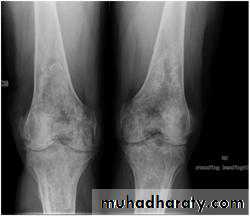

Plain radiography. Anterior-posterior view of bilateral knees. Note the irregular areas of lacy and serpentine calcific deposits in bilateral distal femurs and proximal tibias typical for bone infarcts.